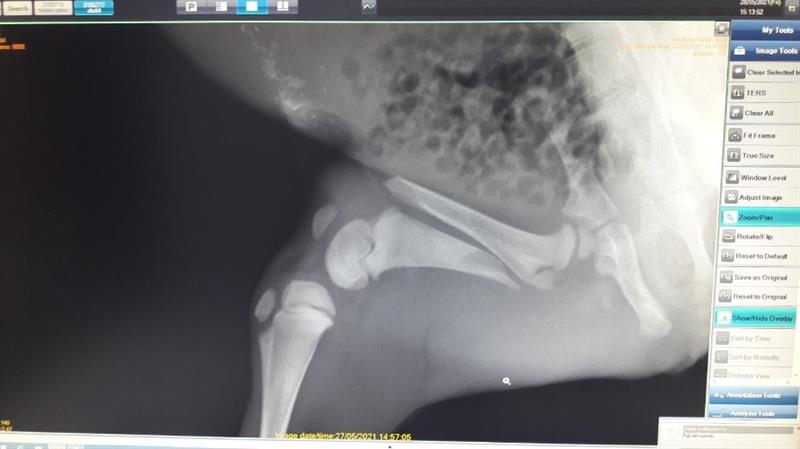

Sinop' un Ayancık ilçesi Mestan köyü Dağ Mahallesi'nde yaralı yavru karaca bulunduğu ihbarını alan DKMP Sinop Şube Müdürlüğü ekipleri ivedilikle olay yerine intikal ettiler. Sağ arka bacağında aksama olduğu fark edilen yavru karaca Şube Müdürlüğü ekiplerince Sarıkum Yaban Hayatı Kurtarma ve Rehabilitasyon Merkezi'ne nakledildi.

Rehabilitasyon merkezinde veteriner hekimce gerçekleştirilen muayenesinde, yavru karacanın yaklaşık 3 haftalık dişi birey olduğu, sağ arka ayak femur kemiğinde kırık bulunduğu ve yoğun şekilde kene enfestasyonuna maruz kaldığı tespit edildi. Ameliyat gününe kadar genel durumunun düzelmesi ve enfeksiyon gelişiminin önlenmesi maksadıyla sıvı elektrolit sağaltımı, vitamin ve antibiyotik tedavisine başlanılan yavru karacanın kırık kemiğinin çevre dokulara zarar vermemesi için de bacağı sargı altına alındı.

Genel durumunun düzelmesinin ardından ameliyatta alınan yavru karacanın kırık femur kemiğine intramedullar pin ve serklaj tel uygulaması yapıldı. Oldukça başarılı bir operasyon geçiren yavru karaca, operasyon sonrası yoğun bakıma alındı. Yavru karaca ertesi gün kendi başına yürümeye başladı.